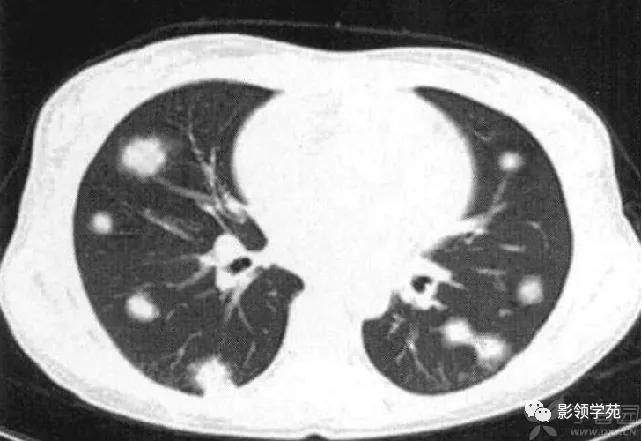

肺内多发结节和肿块是肺Wegener肉芽肿最常见的影像征象,表现为两肺散在分布、多发大小不等类圆形结节或肿块影,以两肺中下野分布多见。部分结节和肿块内可见空洞,洞壁多较厚,内缘光滑或不规则,空洞呈边缘性强化。合并感染时空洞内可形成液-气平面。结节或肿块周围一般都有较短毛刺,部分病灶有长毛刺与邻近的胸膜相连,表现为胸膜凹陷征。这与病理上结节周围存在大量成纤维细胞以及以纤维化形式愈合有关。

结节或肿块周围可见晕轮征、供养血管征。晕轮征提示肺结节或肿块出血,CT表现为结节或肿块周围磨玻璃密度影;供养血管征CT表现为血管影进入结节或肿块内,提示病变以血管为中心生长。

病例1:双肺多发大小不等结节,右肺中叶结节周围见晕轮征及供养血管征。